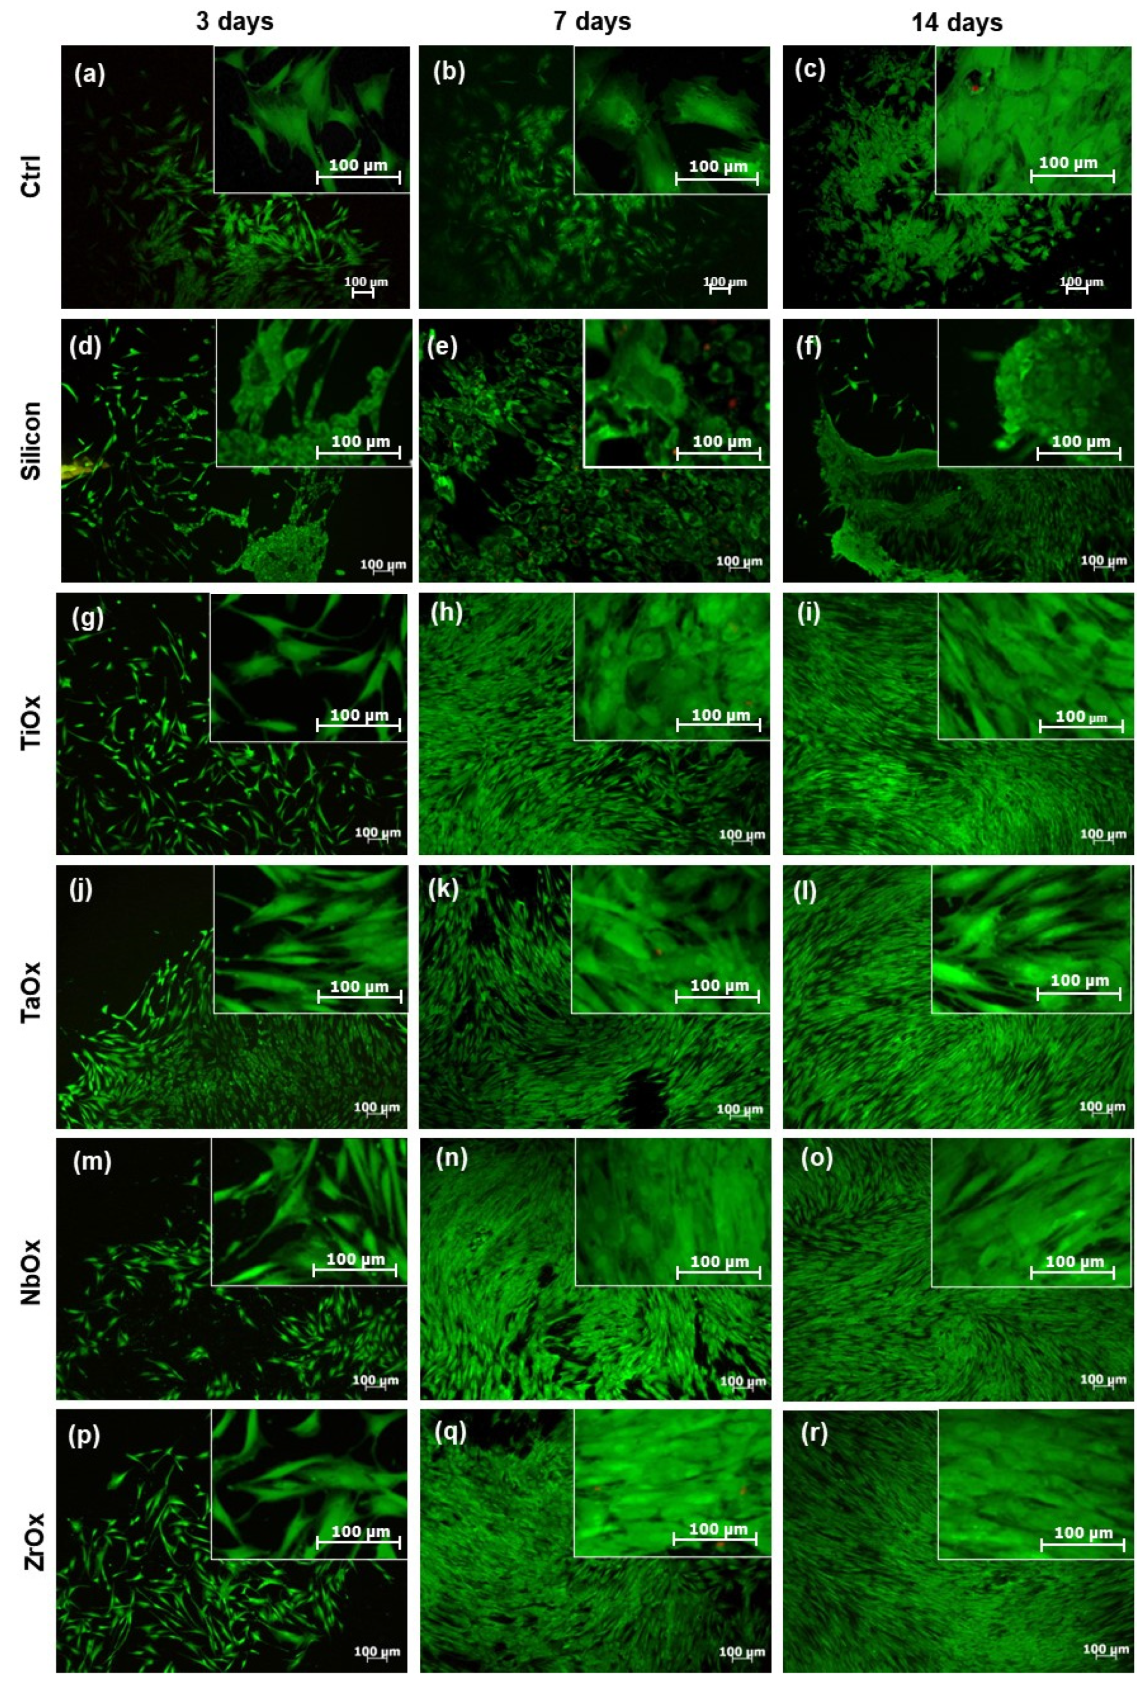

3.3. Viability of BM-MSC Cultured on the Surface of the Coatings

3.4. Proliferation of BM-MSC Cultured on the Coatings